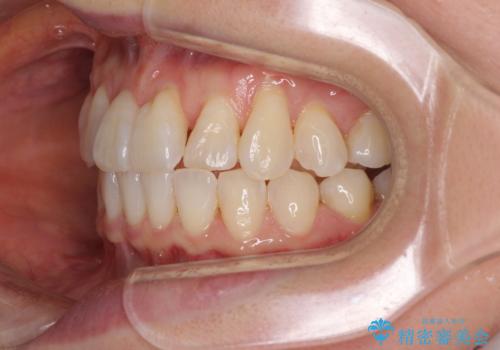

前歯のクロスバイト インビザライン矯正で改善

- むし歯治療を契機に、長年気にしていた前歯のクロスバイトの改善を希望された患者様です。

汚れが溜まりやすく、歯ぎしりがうまくできないため、インビザラインを用いて矯正治療を行うこととしました。

インビザラインによる前歯のクロスバイトの改善は、治療期間中に前歯でしか咬めない時期が続いたり、歯肉退縮や歯髄壊死のリスクが高まったりと、治療中にトラブルを抱えることがあります。

特に上顎側切歯(真ん中から2番目の歯)が舌側に引っ込んでいるケースは、インビザラインでは改善しきれないことがあると言われています。